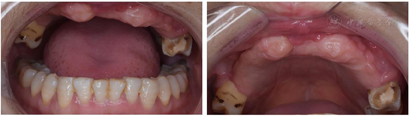

种植体周围角化黏膜厚度不足可导致牙槽嵴边缘骨吸收,增加种植体周围疾病的发病风险,不利于种植体周围组织健康。目前研究认为采用软组织移植术等方式可有效增加种植体周围角化黏膜厚度,改善种植体周围软组织健康状况,提高种植成功率。由于颌骨创伤和骨折术后感染、多次手术等因素,上颌缺牙区种植体唇侧角化黏膜不足2mm,上唇唇珠丧失(图9)。设计在种植体达到骨结合时,制备双侧硬腭角化黏膜游离移植增宽种植体唇侧角化黏膜量,重建患者上颌前庭沟。手术设计上颌前牙种植区牙槽嵴顶黏膜切口,骨膜上向唇侧钝性分离至前庭沟底,将唇侧游离黏膜与前庭沟底骨膜缝合固定,显露受区创面。为减轻术后供区疼痛不适故保骨膜上制取双侧上颌第二磨牙至尖牙对应腭侧角化黏膜,将其植入受区骨膜上(图9.1)。同期,应用自体脂肪充填术纠正外伤术后唇红畸形(图9.4)。术后2个月可见愈合基台唇侧角化黏膜宽度显著增加(图9.2)。

专科检查:双侧颧骨、下颌角过大,面中部凹陷。上唇唇正中可见术后瘢痕,红唇菲薄、唇珠消失(图1)。恒牙列,16-25缺失,17近中牙根外露,I°松动,26牙近中牙冠缺损。患者缺牙区牙槽突不平整,前庭沟变浅,水平向、垂直向咬合关系丧失(图2)。